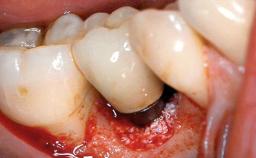

Peri-implant Carcinoma

Maximilian Moergel, Peer Wolfgang Kämmerer, Bilal Al-Nawas

Oral implants are highly successful and offer long-term benefits, especially in the rehabilitation of edentulous patients or patients with oral defects following ablative tumor surgery (Albrektsson and coworkers 1986), and also after radiation therapy (Schiegnitz and coworkers 2014). With the number of implants placed globally going into the millions, implant dentists have observed some rare adverse events. Although carcinogenesis around implants is an exceedingly rare phenomenon, we recently reported about 15 patients treated for carcinomas adjacent to implants at our clinical department over a period of fifteen years (Moergel and coworkers 2014). The following case represents a patient of this cohort; it discusses possible risk factors and makes suggestions for a recall schedule. A 70-year-old woman was referred to our outpatient department for evaluation of a rapidly growing macroscopic alteration of the mucosa in the left mandible.